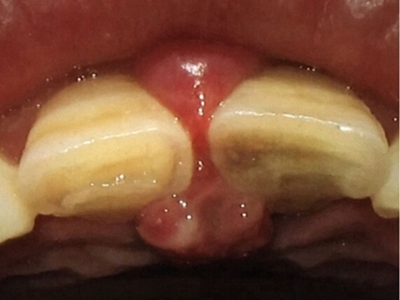

牙龈瘤是指发生在龈乳头部位的炎症反应性瘤样增生物,好发于女性,前磨牙区最为常见。牙龈瘤来源于牙周膜及牙龈的结缔组织,因其无肿瘤的生物学特征和结构,故非真性肿瘤,但切除后易复发,因此切除务必彻底,必要时拔除相关牙齿。

牙龈瘤多发于女性,以青年及中年人为常见,多发生于牙龈乳头部,位于唇、颊侧者较舌、腭侧者多,最常见的部位是前磨牙区。肿块较局限,呈圆形或椭圆形,有时呈分叶状,大小不一,直径由几毫米至数厘米。

肿块有的有蒂,如息肉状;有的无蒂,基底宽广,生长较慢,但在女性妊娠期间可能迅速增大。较大的肿块可以遮盖一部分牙及牙槽突,表面可见牙压痕,易被咬伤而发生溃疡,伴发感染。随着肿块的增长,牙槽骨壁逐渐被破坏,牙可能发生松动、移位。